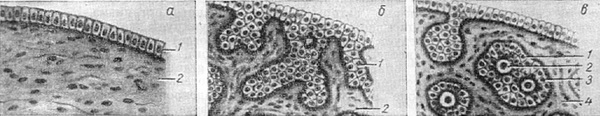

Рис. 1. Розвиток яєчника: а - зачатковый епітелій (1 - епітелій, 2 - мезенхима); б - розростання зачаткового епітелію, індиферентна стадія (1 - пфлюгеровские тяжі, 2 - мезенхима); в - розвиток яєчника з індиферентної статевої залози (1 - яйцевые кулі, 2 - овогонии, 3 - фолікулярні клітини, 4 - мезенхима).

Розвиток статевого зачатка (валика) в напрямку яєчникової гонади полягає в тому, що епітелій починає вростати в підлягає мезенхиму у вигляді щільних клітинних тяжів (рис. 1). Розростаючись, статева залоза поступово відособляється від вольфова тіла. На цій стадії розвитку первинна гонада ще має індиферентний характер. Спеціальне розвиток яєчника починається з кінця другого місяця ембріонального життя і закінчується тільки в постэмбриональном періоді. Щільні епітеліальні тяжі індиферентної статевої залози, вростаючи в мезенхиму, разобщаются останньої на відокремлені клітинні групи («яйцевые» кулі). Клітини кожної з таких груп розташовуються таким чином, що одна з них, первинне яйце (овогония), розташовується в центрі, а інші - на периферії клітини в один ряд (клітини яйцевого епітелію). Вся освіта в цілому носить назву первинного (примордиального) фолікула. Спочатку фолікули розкидані у великій кількості по всьому яєчника. Надалі центрально розташовані фолікули гинуть, залишаються тільки фолікули, розташовані в периферичних частинах статевої залози (кірковий шар дефинитивного яєчника).